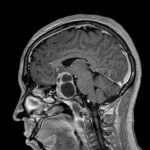

Los traumatismos —entendidos como cualquier lesión física resultante de una fuerza externa que supera la capacidad de resistencia del organismo— representan un desafío persistente y complejo para la salud pública global. A pesar de los avances en medicina, transporte y seguridad, los traumatismos continúan siendo una de las principales causas de muerte y discapacidad en todo el mundo, afectando a millones de personas cada año. Esta realidad se debe a múltiples factores interrelacionados: cambios demográficos, patrones de movilidad, desigualdades socioeconómicas, estilos de vida y condiciones ambientales que predisponen a eventos traumáticos. Según estimaciones recientes, los traumatismos y la violencia causan cerca de 4.4 millones de muertes anuales, lo que equivale aproximadamente al 8 por ciento de todas las defunciones globales cada año.